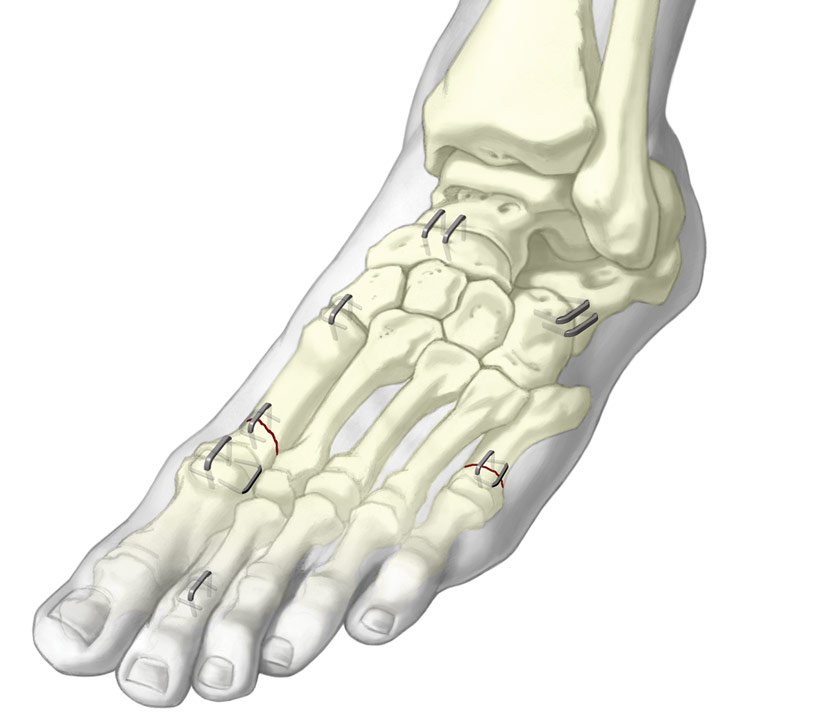

Grapas de Nitinol para Pie

Las grapas de Nitinol superelásticas ofrecen una compresión continua y dinámica durante la curación.

• No requiere calefacción ni refrigeración para la compresión.

• Varios tamaños con diseños simétricos y asimétricos.

• Se utiliza para fracturas, osteotomías y fusiones de huesos pequeños en la mano y el pie.